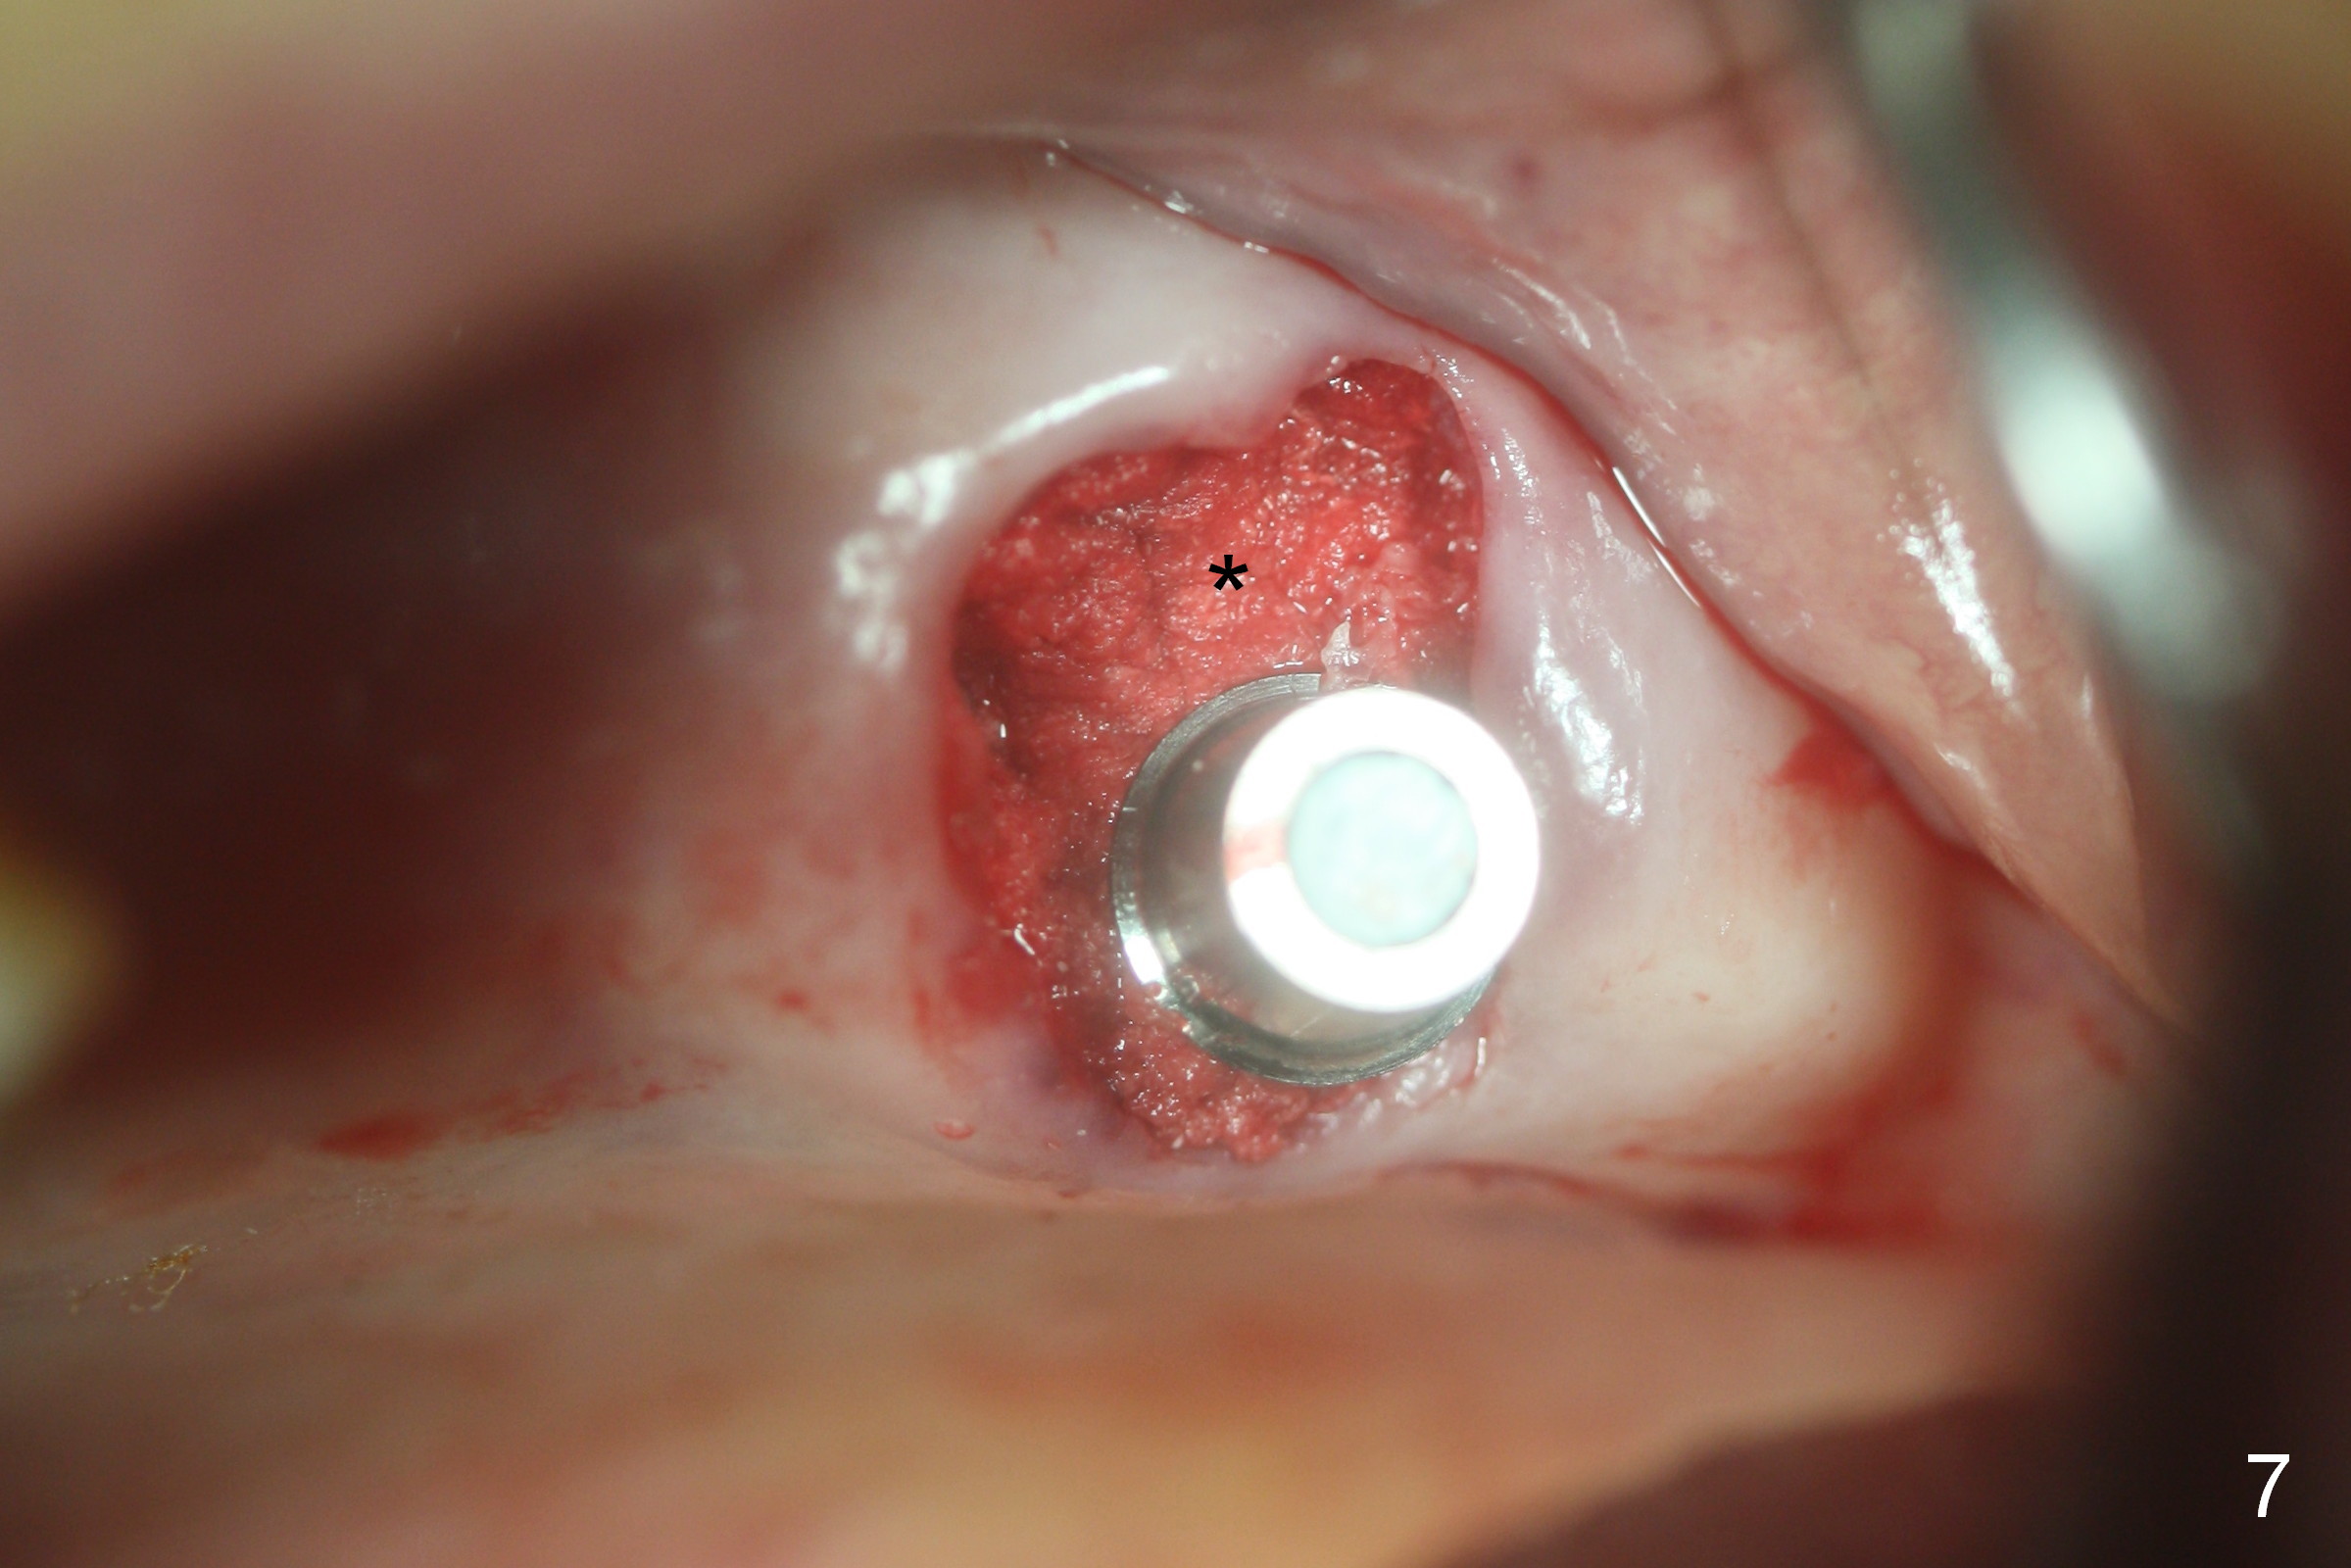

Fig.1,2 show the close relationship of the upper flipper and the residual roots at #15. Atraumatic extraction using periotomes and surgical sectioning still results in perforation of the mesiobuccal socket (Fig.3 >). The distobuccal one is shallow, while the septum is small. It appears that the palatal (Fig.3 P) socket is the most ideal recipient site for the immediate implant and is expanded with Magic Osteotomes until 4.3 mm (Fig.4,5) with the coronal end pushed as buccal as possible. After placing allograft for sinus lift (Fig.6 >), a 5x11 mm IBS implant is placed with insertion torque ~ 50 Ncm. A 6x4(3) mm pair abutment is placed, followed by bone graft in the remaining sockets (Fig.6 *) and by Osteogen plug (Fig.7 *). Finally the socket is sealed by applying acrylic over the abutment (Fig.8). While the acrylic is setting, the flipper is seated and excess acrylic is removed and pushed away from the flipper (Fig.9). Advise the patient not to wear the flipper. If it is being worn, there will be minimal contact between the flipper and the immediate provisional.